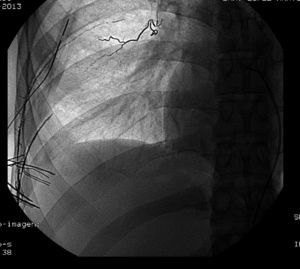

After 24h, the patient's general condition worsened, with no vesicular breath sounds in the right hemithorax, blood pressure 90/60, and drainage of more than 800ml of bloody fluid at more than 400ml per hour. Chest CT scan with intravenous contrast demonstrated right pneumothorax with the drain tube and a voluminous fluid level (hemopneumothorax), which was causing compression atelectasis of the right lower lobe. The pneumothorax cavity showed a tract compatible with adhesions, although the bleeding point was not identified. The study was completed with intercostal arterial embolization, and, given the suspicion that the origin of the bleeding was the intercostal arteries of the intercostal space through which the drain tube entered into the thoracic cavity, we decided to perform embolization of their distal ends (Fig. 2). The total discharge was 2100ml bloody fluid; blood work showed a hemoglobin level of 8.6g/dl, requiring blood transfusion and volume replacement. During post-op, the patient progressed favorably from a radiological and clinical standpoint and the tube was withdrawn after 10 days.